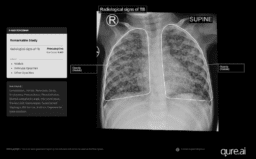

![]() | CE mark for India-made AI for screening TB in toddlersMobiHealthNews - (Wednesday October 29, 2025) - Frequent Updates / MobiHealthNews | |||